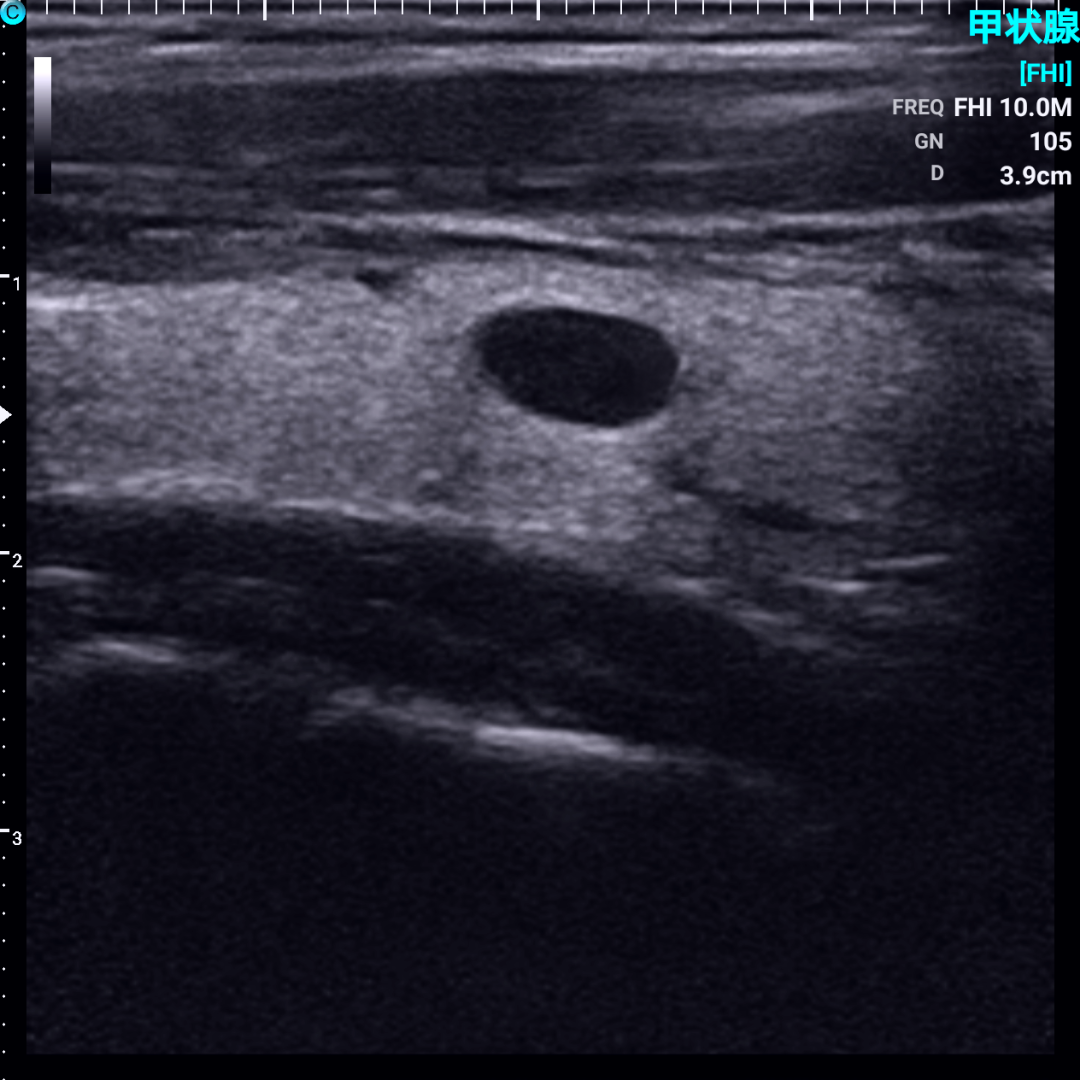

甲状腺结节超声图像解读?

对于已经发现甲状腺结节或怀疑甲状腺结节的患者,超声检查是首选的检查方法。

正常甲状腺超声图像和甲状腺结节超图像